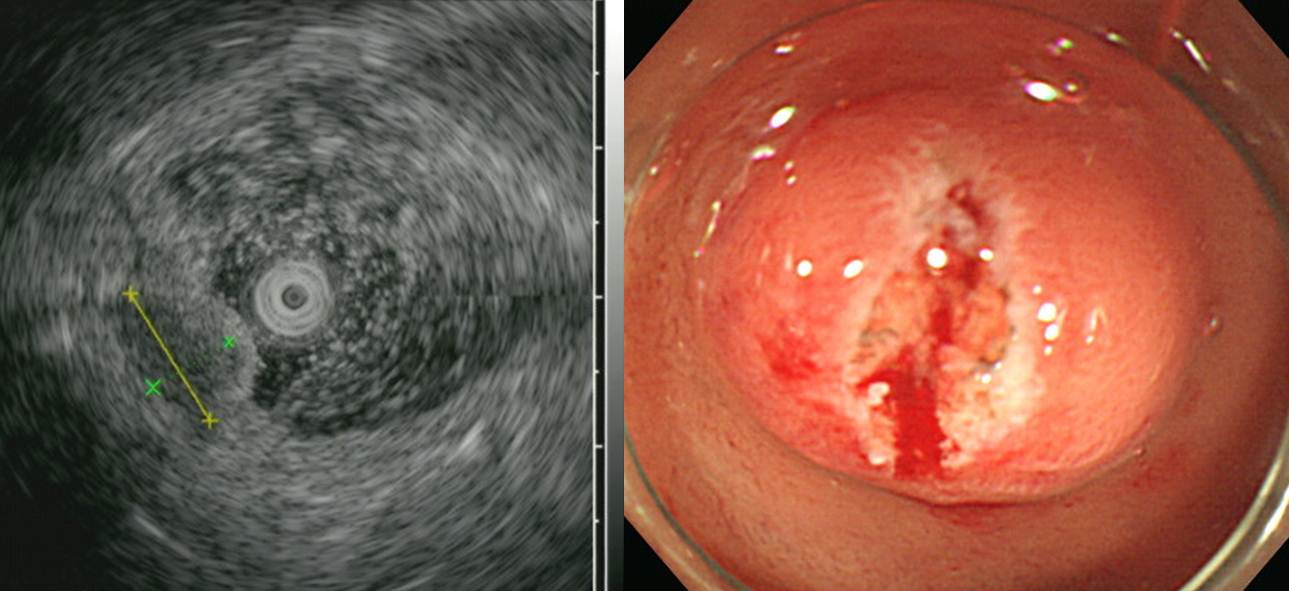

ÇÔ¸ôÇü ½ÊÀÌÁöÀå À¯¾ÏÁ¾À¸·Î ³»½Ã°æ ÀýÁ¦°¡ ½±Áö ¾ÊÀº ¸ð¾çÀ̾ú½À´Ï´Ù. Á¶Á÷°Ë»ç °á°úµµ neuroendocrine tumor with suspicious tumor emboli¿´½À´Ï´Ù. ¼ö¼úÀ» ÇÏ¿´½À´Ï´Ù.

SmallTODAY 021

Well-differentiated neuroendocrine tumor (G1)

1. Name of Procedure: Duodenal wedge resection

6. Size: 0.7x0.4 cm